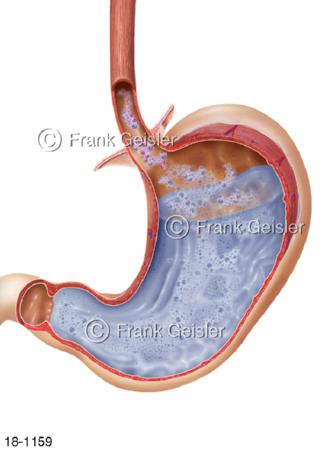

18-1159 Sodbrennen Reflux in Magen Speiseröhre